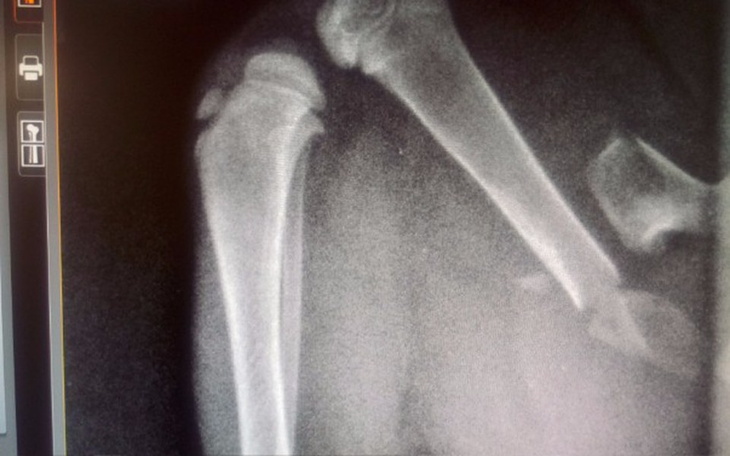

Nie dość że od najmłodszych tygodni bezdomna, bez mamy, bez rodziny, w zimnie, porzucona.... to jeszcze ma paskudnie złamaną tylną łapkę. Łapka złamana jest w dwóch miejscach.

Lekarz zdecydował podjąć się zoperowania tej łapki. Dziś 22.11.2018 wieczorem zawożę ją na operację do Łodzi.